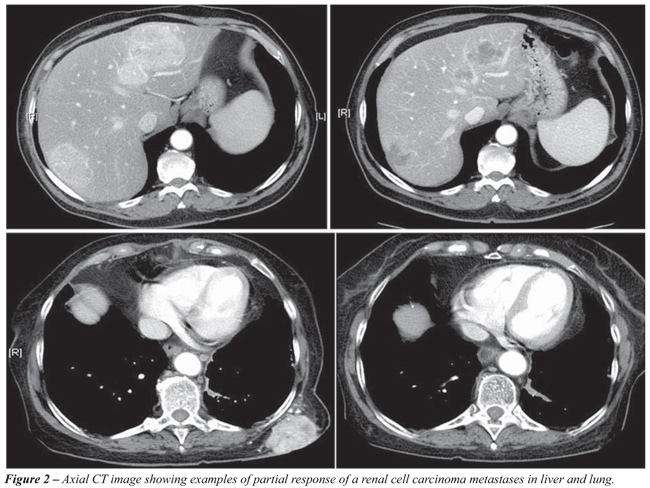

Such response rates, measured by RECIST criteria, had not been observed in second-line treatments in the conventional immunotherapy era. Figure-2 shows an example of partial response with Sunitinib that is the new standard of care for mRRC.

A phase III trial comparing IFN-alpha and Sunitinib as first-line treatment for mRCC was recently completed. 750 patients were enrolled and randomized, 90% had undergone prior nephrectomy. The average PFS was longer in the Sunitinib group compared with the IFN group (11 vs. 5 months). Only one case of complete response was observed in Sunitinib group (22). Although not yet published, survival data analysis was orally presented in the 2008 American Society of Clinical Oncology (ASCO) Annual Meeting showing a survival benefit in favor of Sunitinib (23).